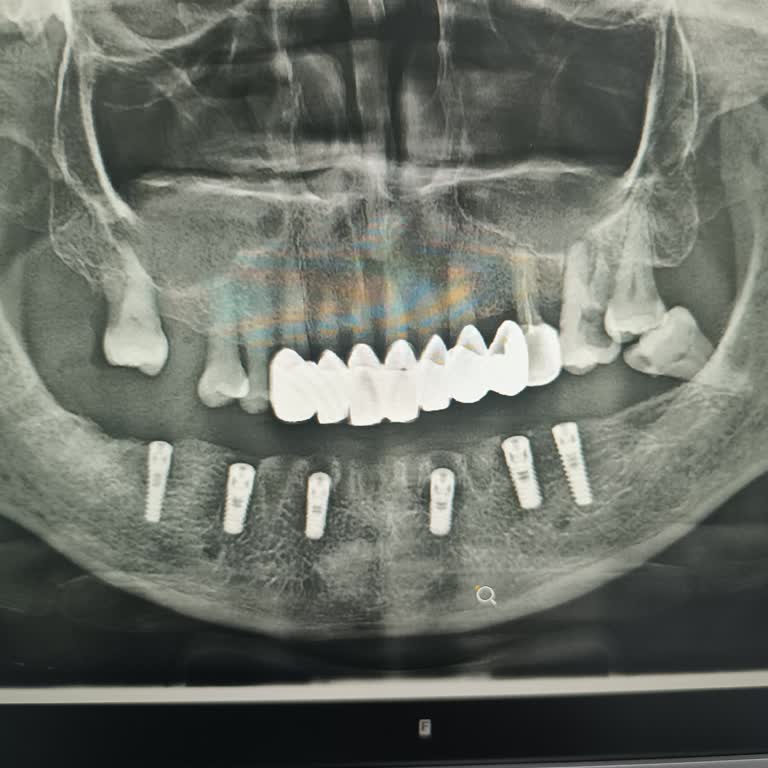

2022 Ocak ayında İstanbul Bağcılar Erkut Ağız ve Diş Sağlığı Merkezi’nde E***** E*** tarafından gerçekleştirilen implant işlemi sırasında, işlem öncesi ve sonrası röntgen çekilmeden uygulama yapıldı. Bu nedenle implant yanlış yerleştirildi ve sinir hasarı oluştu. İşlem için IBAN üzerinden 4.000 TL ö...